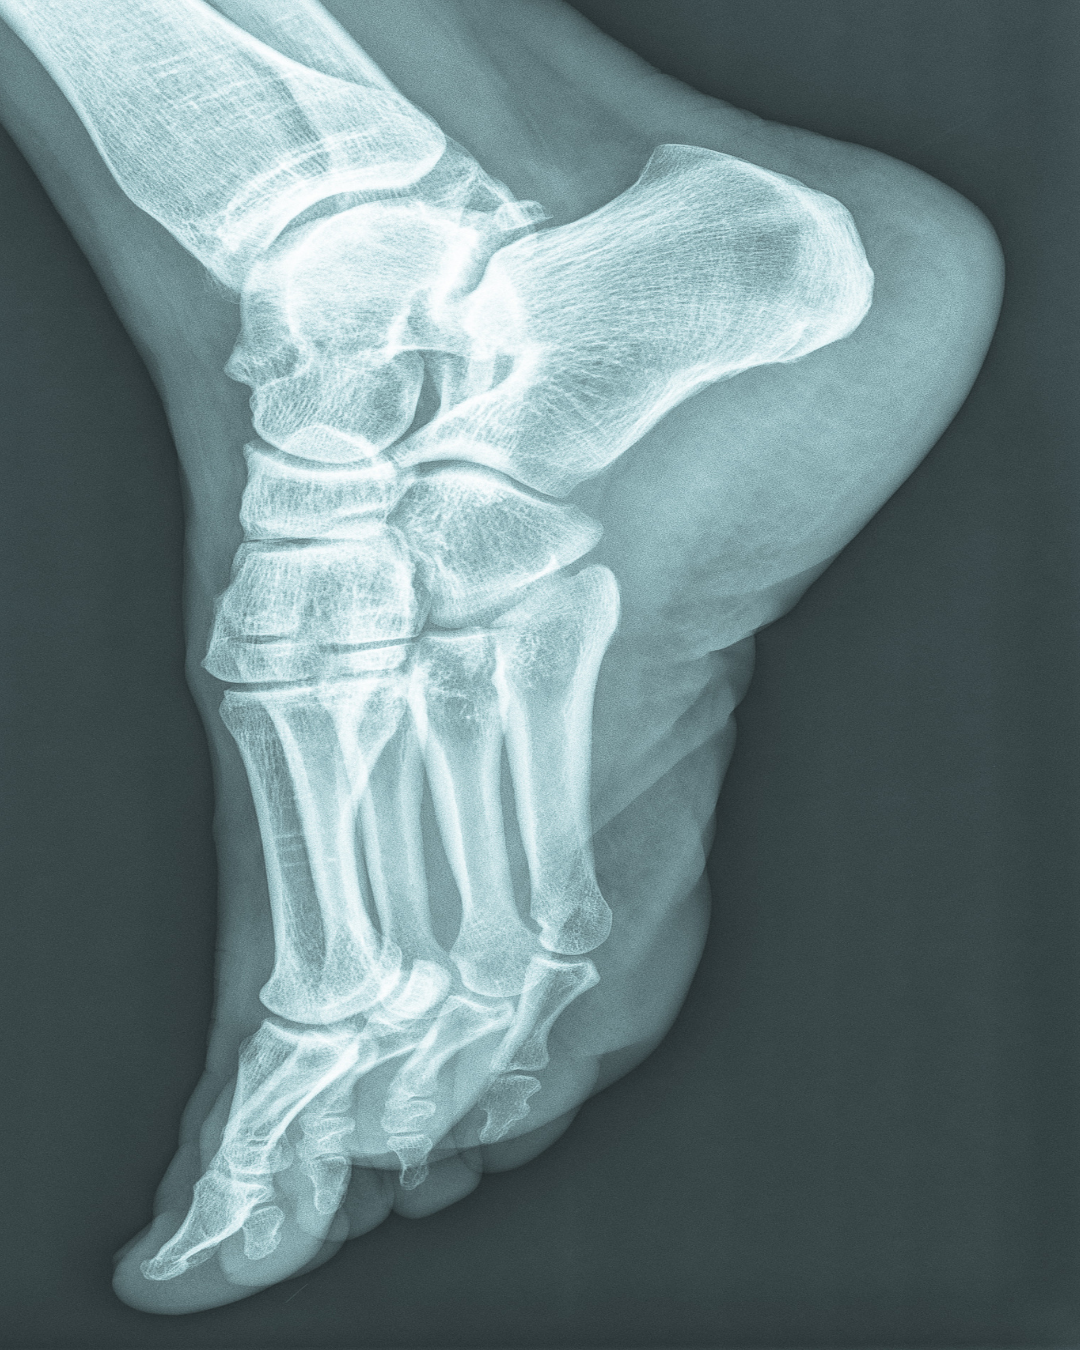

The foot contains multiple bones, connected by ligaments, capsules and muscles. Together they form arches, medially and at the front of the foot. A footprint shows a zone where there is no pressure.

The medial arch differs per person: some have ‘a high arch’; others develop throughout life a flat foot. The cause can be genetically, but often the cause is shoes, sport or a (standing) profession.